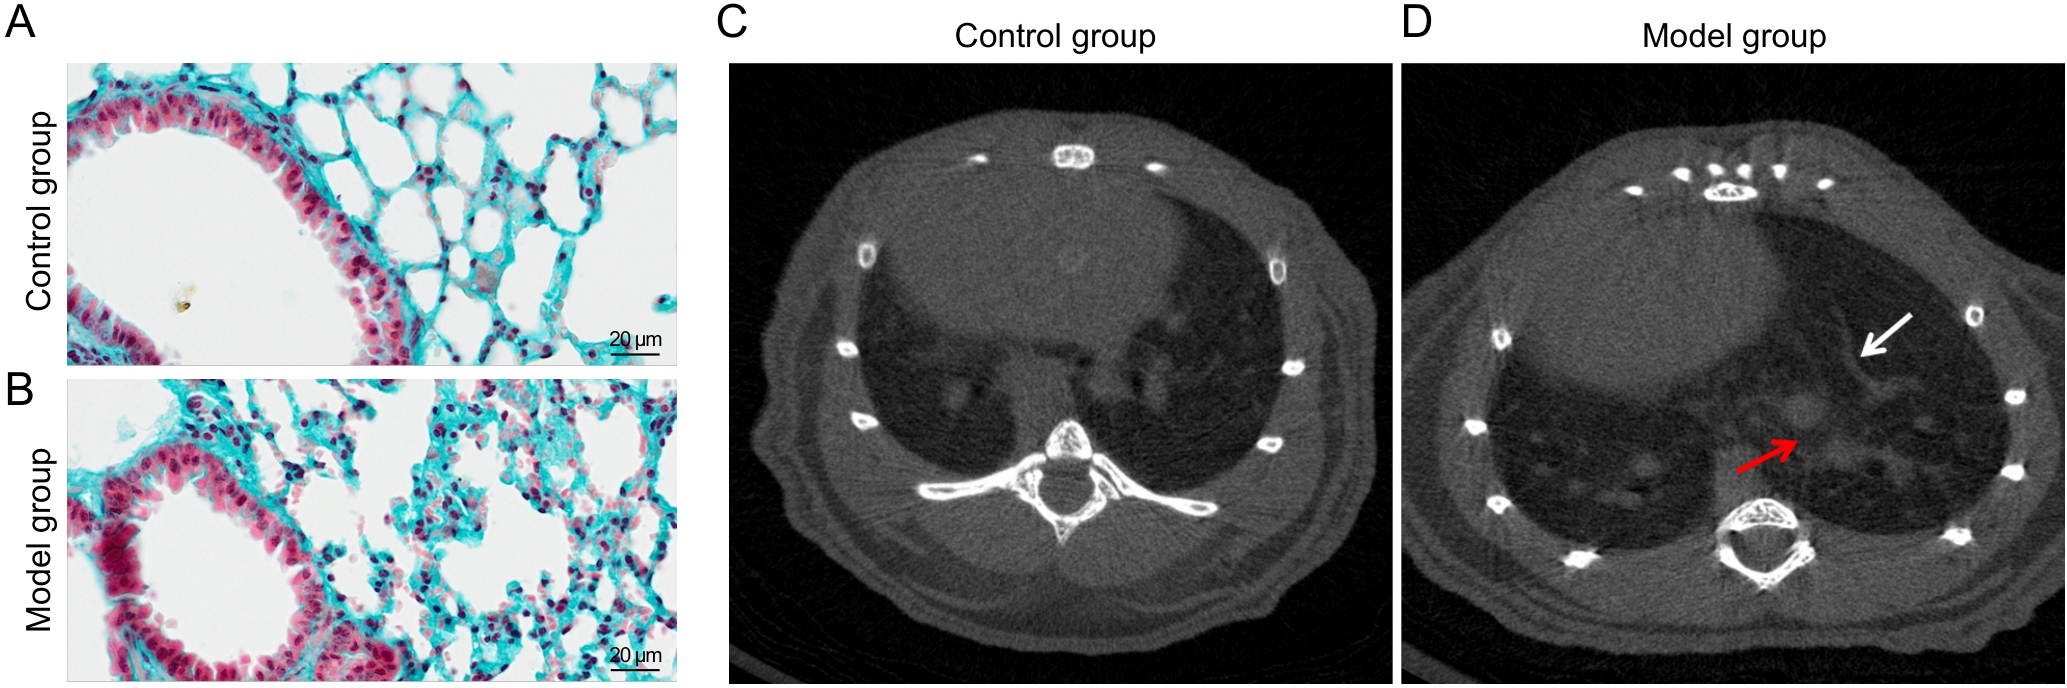

Figure 5 Comparative analysis of pulmonary collagen deposition (×400) and Micro-CT imaging of mice in the control and model groups